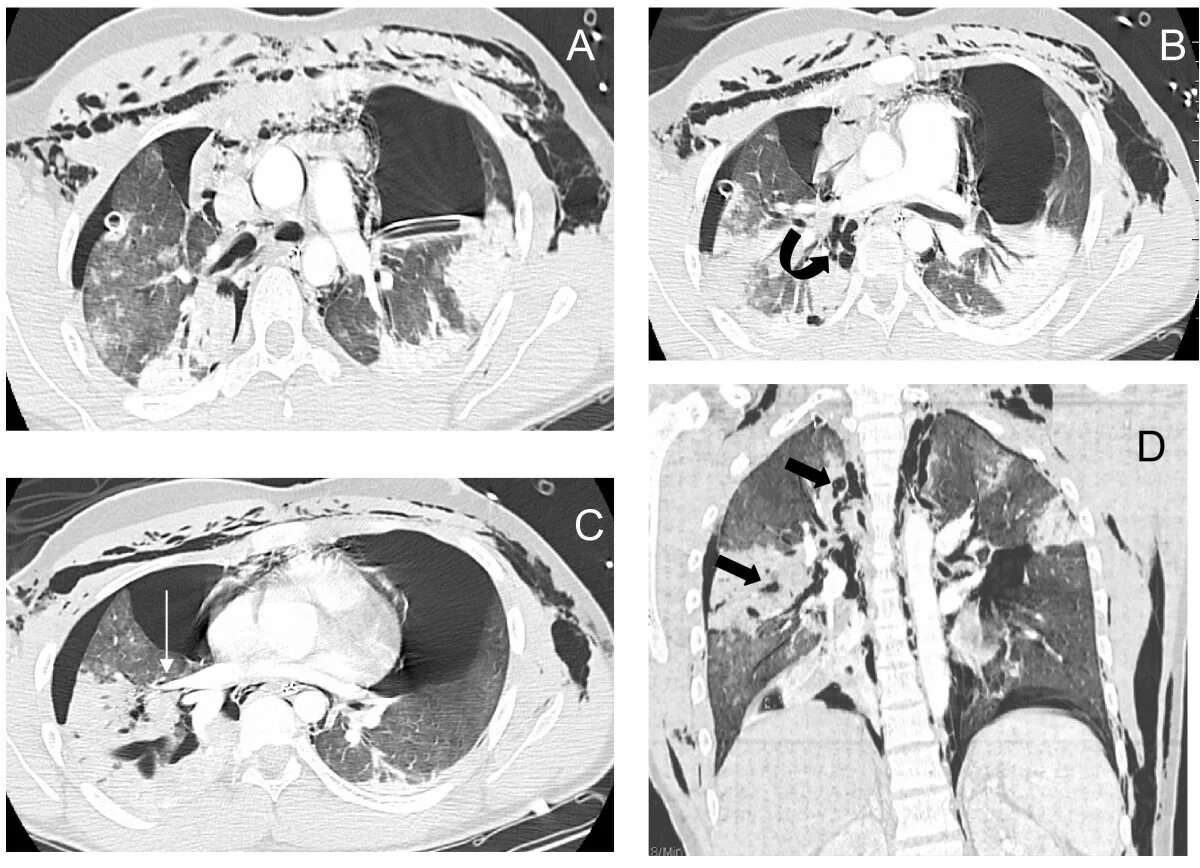

Утолщение бронха